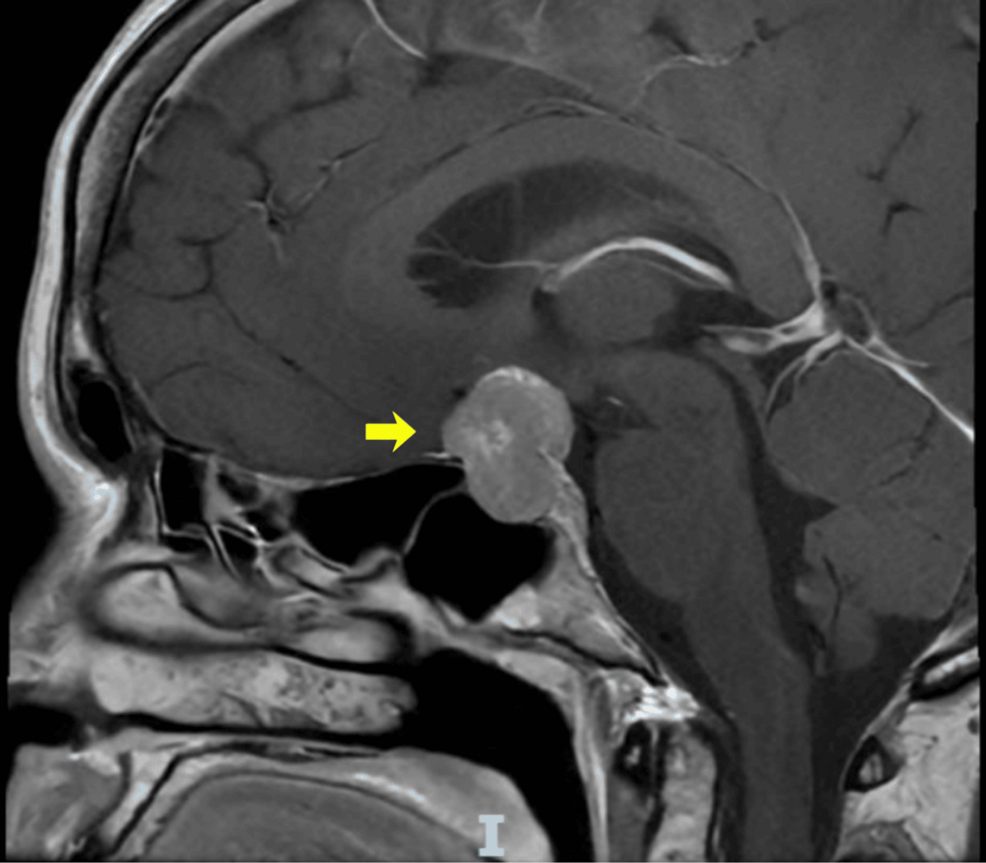

El informe de caso se centra en un paciente que presentó hiponatremia severa debido al síndrome de secreción inadecuada de hormona antidiurética (SIADH). Aunque los adenomas pituitarios pueden causar SIADH y, por ende, hiponatremia, los casos documentados hasta la fecha son pocos. Este caso particular involucra un macroadenoma pituitario.